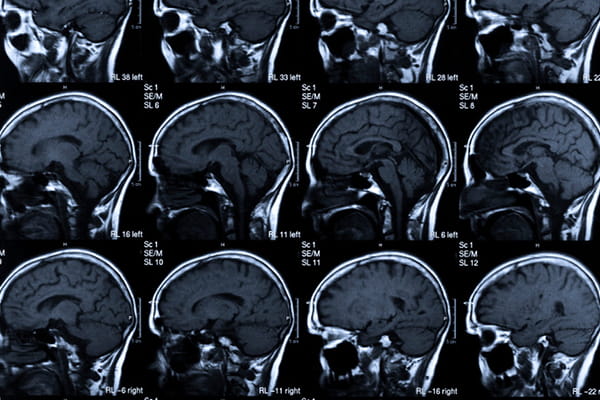

Hearing loss is associated with cognitive decline, though more research is needed to determine the degree of the connection, said Dr. Costantino Iadecola, director of the Feil Family Brain and Mind Research Institute at Weill Cornell Medical College in New York City.

Dementia can develop for a variety of reasons, including vascular, neurogenerative and neuroimmune conditions, Iadecola said. "Each has a different impact on the brain."

One theory behind the connection between dementia and hearing loss is that dementia creates certain conditions that may affect the ability to hear, Iadecola said. Or, he added, it could be the reverse, with hearing loss somehow impairing the brain's ability to function.